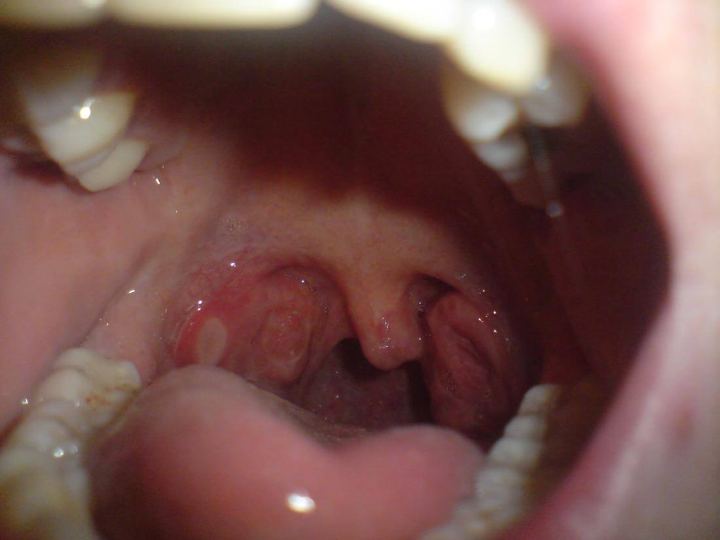

Penyakit menular seksual tidak hanya muncul di bawah kulit, beberapa tanda awal muncul di mulut seperti luka dingin (herpes), bercak putih (sariawan mulut akibat HIV), dan bahkan luka sifilis yang menyerupai sariawan di mulut.

Gejala-gejala ini tidak kentara dan sering disalahartikan sebagai tidak berbahaya, tetapi bisa jadi sistem kekebalan tubuh sedang memberi sinyal.

Kanker mulut

Kanker mulut jarang dimulai dengan rasa sakit. Kanker ini diawali dengan rasa diam seperti luka yang tidak kunjung sembuh, bercak yang berubah warna, atau area yang menebal di dalam mulut yang tidak kunjung sembuh.